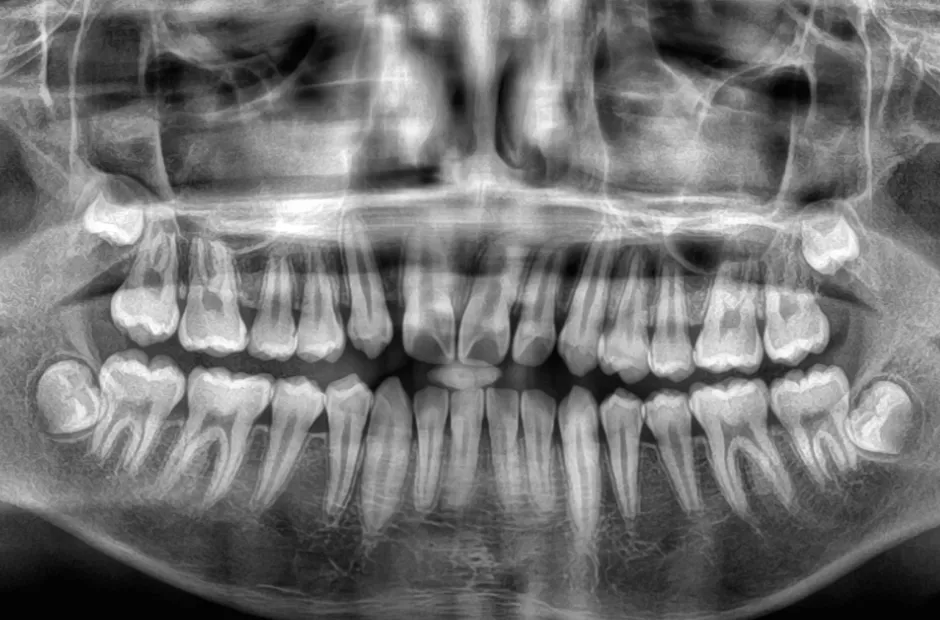

口腔内写真やレントゲンの撮影、歯型取りなど、口や顎の状態を詳しく把握するための精密検査を行ないます。さらに、骨の成長状況や身長・体重の増加傾向、永久歯の生えかわりについても確認します。

治療を始めるタイミング

「子どもの歯並び、いつから治療を始めるべき?」と悩んでいませんか?小児矯正を始めるベストなタイミングは、永久歯が生え始める6歳頃が目安です。この時期から治療を始めると、将来的にワイヤーを使う本格的な矯正(ブラケット治療)が必要なくなったり、治療期間を大幅に短縮できたりします。これは、子どもの顎の成長を利用して歯が並ぶスペースを確保する「短期集中治療」とも言えるでしょう。また、歯並びが悪いと見た目が気になるだけでなく、うまく噛めないといった機能的な問題も生じます。だからこそ、早い段階で矯正を始めることで、これらの問題を改善し、健康な成長をサポートすることが大切です。さらに、先天的な歯や顎の異常を早期に発見しやすくなるため、もし異常が見つかっても、負担の大きい外科手術などを回避できる可能性が高まります。

小児矯正は、発育段階に合わせて1期治療と2期治療の2段階で進めていきます。基本的に1期治療で歯列の土台となる顎の状態を整えた後、2期治療に移行して矯正装置で本格的に歯並びを整えます。なお、ケースによっては1期治療だけで治療が完了する場合があります。また、治療開始時にほとんど永久歯が生えそろっているケースなどは、2期治療から治療を開始する場合もあります。

- Step 06

再検査・再診断

12歳臼歯とよばれる第二大臼歯が上下生えそろったころに、再び歯並びや噛み合わせの状態を詳しく検査します。このときに追加で2期治療が必要か、必要な場合は抜歯せずに治療ができるかという点を診断します。